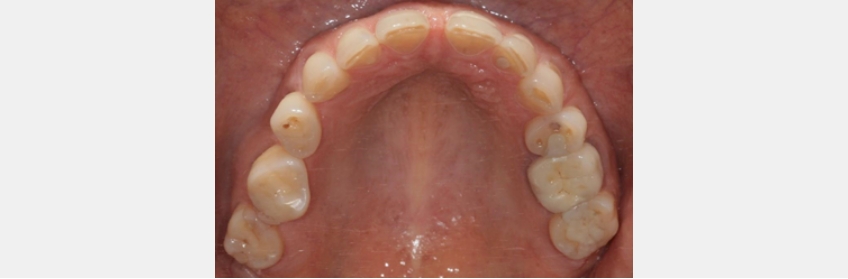

Here’s the proof. Recent studies in the otolaryngology literature are providing dentists with support for a new paradigm. The newest research shows that a narrow, highly vaulted maxilla in the premolar region increases the risk of having obstructive apnea.

In a separate study, it was determined that a narrow maxilla creates palatal or base tongue collapse. Further, the location of the narrowing is linked to different types of blockages: Molar narrowing creates different obstructive points than premolar narrowing. Lastly, if the maxilla is expanded, airway collapse is significantly reduced.